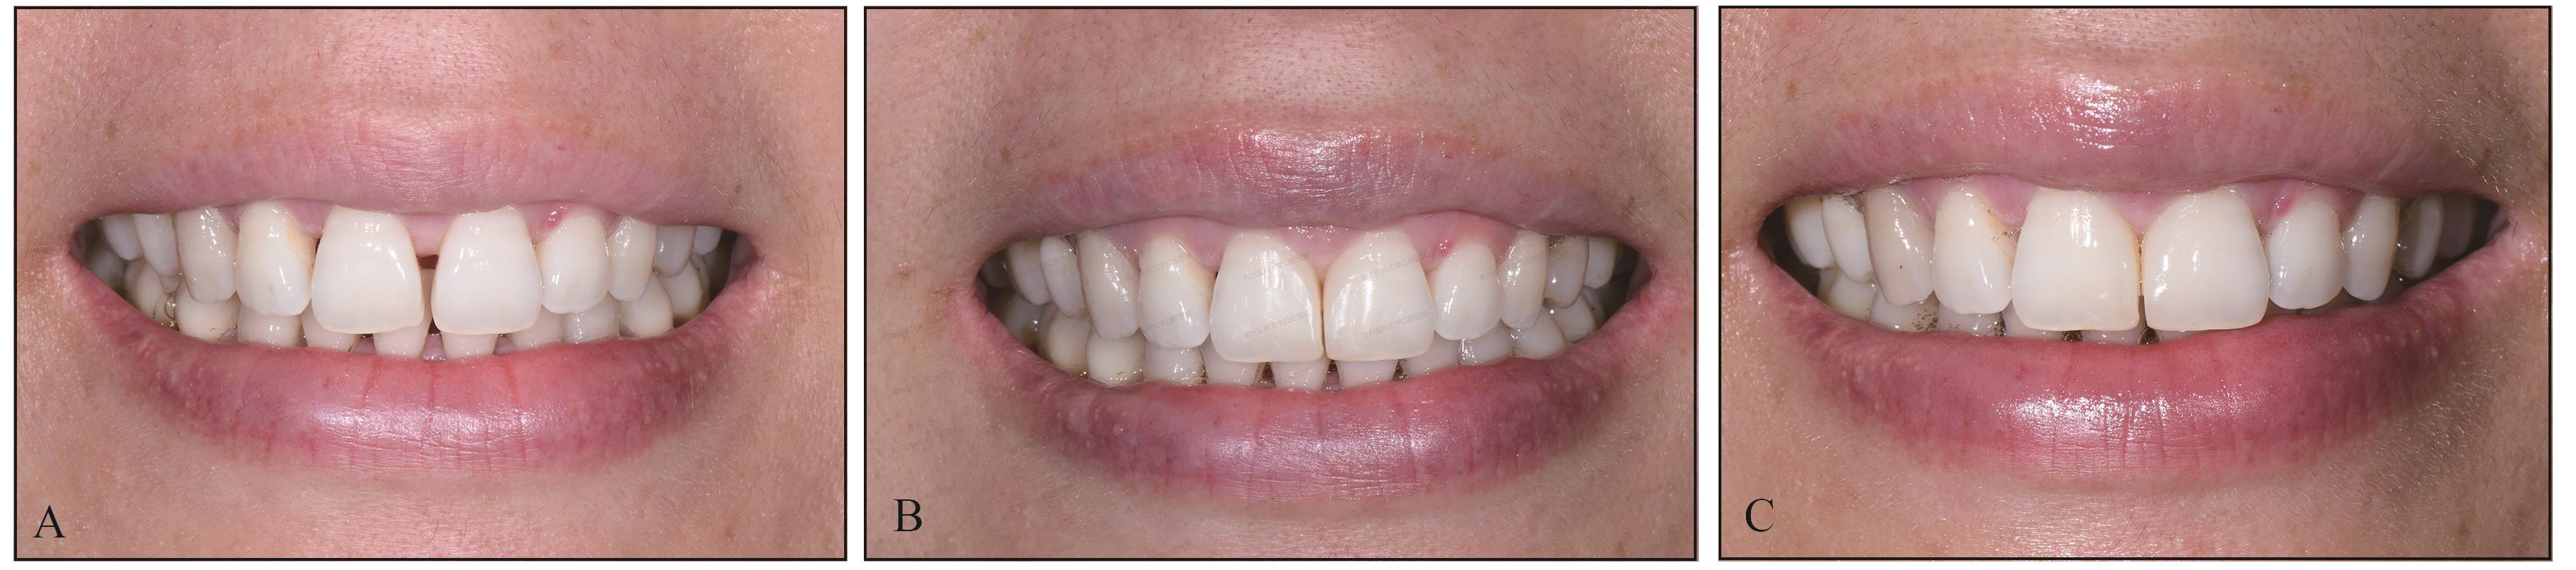

图 2

术前上前牙正面观"